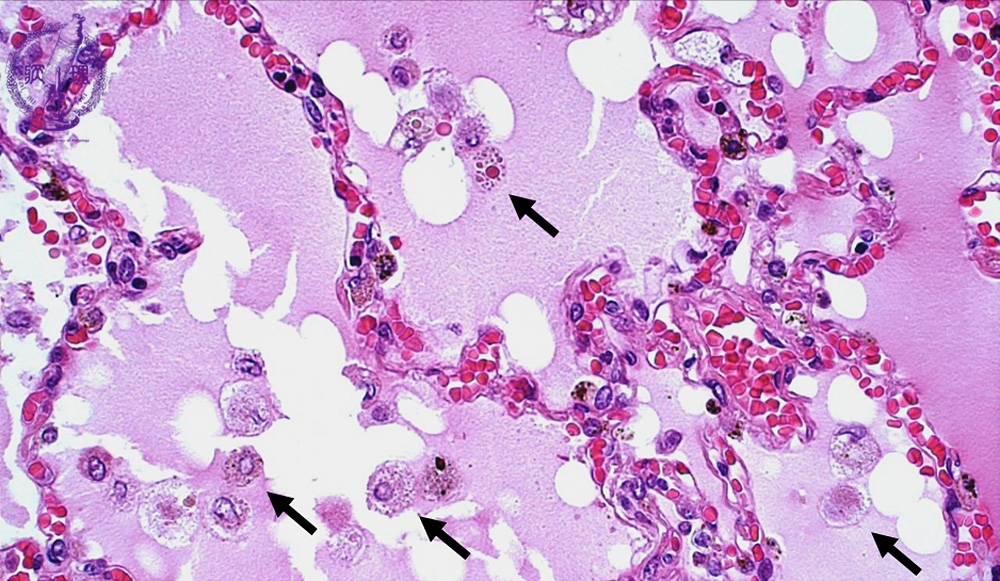

- 5.Lung, Pleura

- ★(1)Pulmonary edema

Microscopic view (HE stain, high power view): In this especially congested area, interalveolar septa show capillaries packed with red blood cells. There are many macrophages (arrow), which phagocytize the leaking plasma transudate and red blood cells.